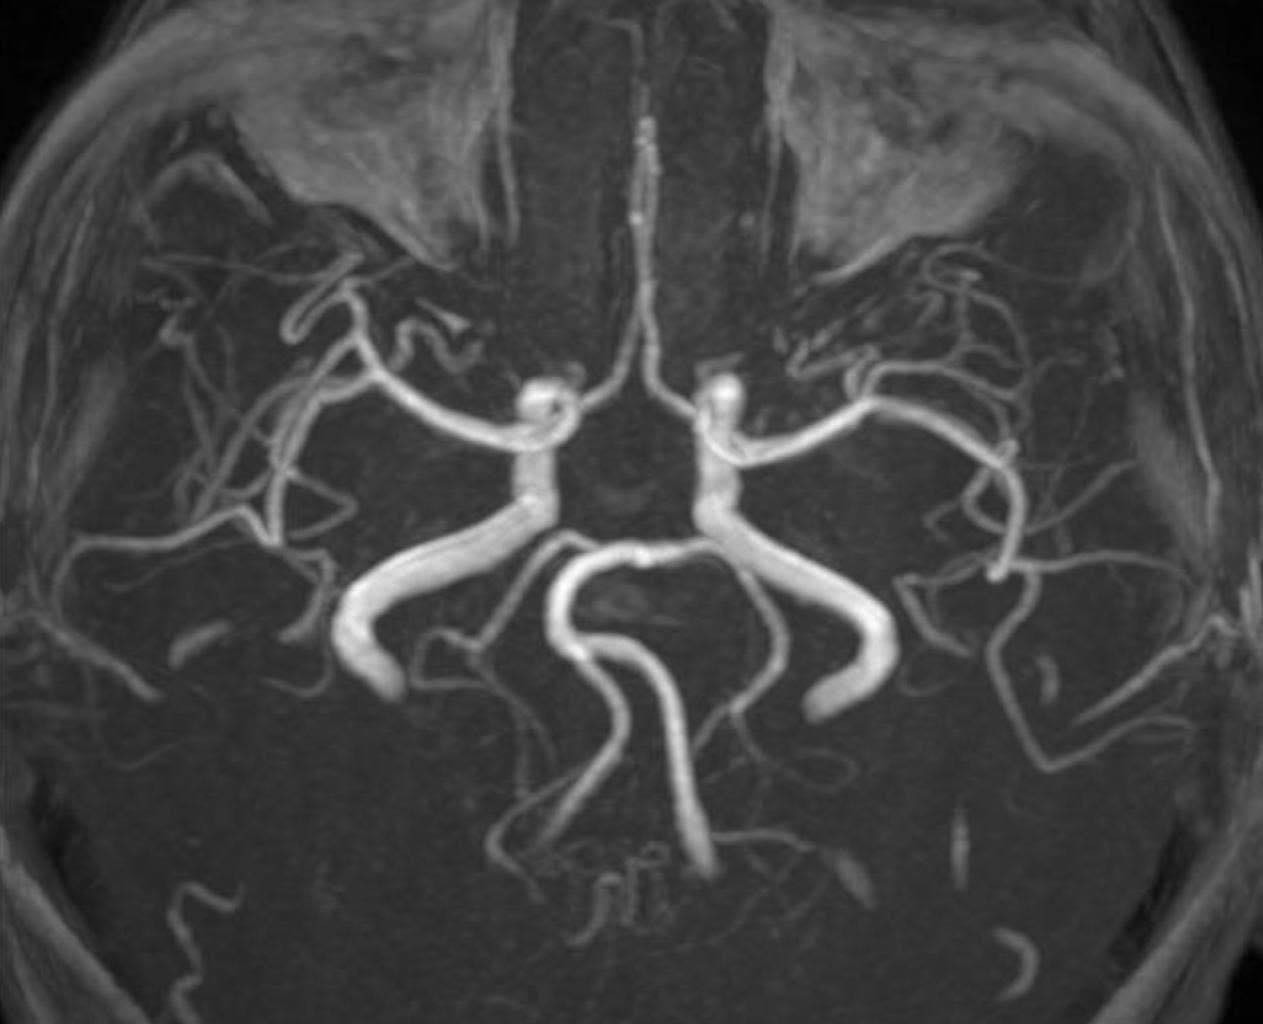

Trên hình ảnh kiểm tra, bác sĩ ghi nhận tình trạng tổn thương não xảy ra ở người bệnh (ảnh: BSCC)

PGS Huy Thắng cho biết, ngay khi nhập viện, người bệnh được chụp MRI não. Hình ảnh cho thấy tổn thương não xảy ra ở hai bên trung tâm bán bầu dục và vùng lồi thể chai. Các thăm dò mạch máu não không ghi nhận tình trạng tắc hay hẹp các động mạch lớn. Dựa trên lâm sàng và hình ảnh học, các bác sĩ chẩn đoán bệnh nhân bị nhồi máu não cấp vùng trung tâm bán bầu dục hai bên và lồi thể chai.